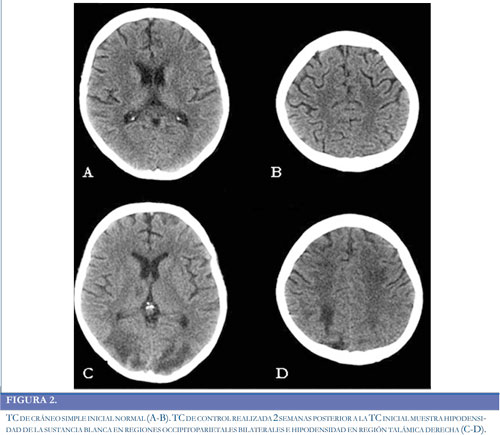

Paciente de 24 años de edad previamente sana, sin antecedentes médicos de importancia, quien ingresó a la institución por sintomatología de 20 días de evolución, consistente en fiebre no cuantificada asociada a disnea progresiva de medianos hasta pequeños esfuerzos y edema de miembros inferiores en los últimos dos días. Intra-hospitalariamente evolucionó con deterioro de la función sistólica y derrame pericárdico que aumentó progresivamente. Durante la estancia en la Unidad de Cuidados Intensivos (UCI), la paciente presentó hipotensión, inestabilidad hemodinámica, necesidad de soporte vasopresor y requirió reanimación cardiopulmonar y asistencia ventricular izquierda. Se confirmó diagnóstico de miocardiopatía chagásica aguda y se llevo a trasplante cardíaco ortotópico de urgencia, iniciándose medicación inmunosupresora con corticoides, basiliximab y micofenolato, como parte del manejo del paciente trasplantado. El inicio del tacrolimus se realizo de forma tardía (1 mes después del trasplante), debido a previa falla renal que requirió hemodiálisis. Permaneció un mes en UCI al cabo del cual y sin compromiso neurológico previó, inicio somnolencia sin una causa aparente, por lo que se decidió realizar una tomografía computada simple (TC) de cráneo, sin observar anormalidades (Figura 2A-2B). Tras presentar mejoría clínica, fue trasladada al servicio de hospitalización general. Dos días después del traslado manifestó cefalea global intensa asociada a irritabilidad, ansiedad y elevación de las cifras tensionales con un difícil control de las mismas (Figura 3). Posteriormente presentó dos episodios convulsivos tónico-clónicos generalizados de 2 minutos de duración con desviación de la mirada a la izquierda, los cuales cedieron a la administración de midazolam e infusión de fenitoína. Los paraclínicos, incluidos electrolitos y pruebas de función hepática, renal y el análisis del LCR se encontraron dentro de parámetros normales. Se realizó una nueva TC de cráneo en la que se observaron hipodensidades de la sustancia blanca comprometiendo regiones occipito-parietales bilaterales y región talámica derecha (Figura 2C-2D). Las imágenes por Resonancia Magnética (IRM) confirmaron el compromiso de la sustancia blanca con lesiones hiperintensas en las secuencias T2 y FLAIR a nivel frontal, parietal y occipital bilaterales, así como en región talámica derecha, considerando cuadro compatible con SEPR (Figura 4A-4D). Adicionalmente se realizó medición de niveles plasmáticos de tacrolimus, encontrando marcado aumento de los mismos. Se suspendió la administración de eritropoyetina y se realizó cambio de tacrolimus a everolimus y se ajustaron las dosis de prednisolona. Después de las primeras 24 horas tras realizar estos cambios presentó recuperación de su estado de conciencia y resolución de su cuadro clínico, sin nuevos episodios convulsivos, ni otras manifestaciones neurológicas. La RM cerebral realizada un mes después del deterioro neurológico, mostró una resolución completa del compromiso de la sustancia blanca posterior (Figura 4D-4G).